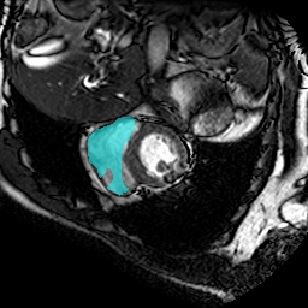

For CMR dataset, we only consider setting 1 because setting 2 is difficult to implement. The results are shown in Table 1 and Figure 4. In general, our proposed method is superior than others. For CHAOS dataset, we consider both setting 1 and setting 2. From the results, we can see the performance of our proposed model is higher than others on CHAOS and CMR datasets. Compared with Q-Net, our mean dice score on CHAOS dataset achieves about 82%. The segmentation results of the model are shown in Figure 5. In setting 2, the slices of the objects containing the test classes are all removed at training stage, and our model still performs well. As can be seen from the Table 2, the segmentation effect of the model on the right kidney is slightly worse than that of ALPNet, but overall, we achieve the best performance. The specific segmentation results are shown in Figure 6. As can be seen from the figure, other methods have excessive segmentation, but ours does not. Our segmentation results are more accurate and reduce redundant segmentation.